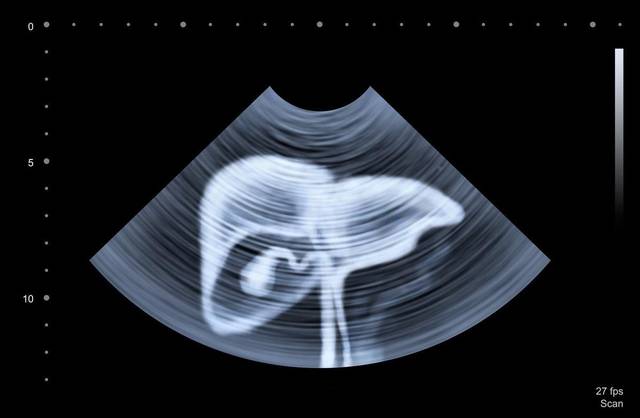

比如说常见的脂肪肝,就是因为脂肪在肝内堆积太多,影响了肝功能。这时候需要“管住嘴,迈开腿”,增加运动就可以很好的减轻脂肪肝。华子自己曾经有一段时间脂肪肝就很严重,后来天天骑行运动,用了一年的时间,脂肪肝就消失了。